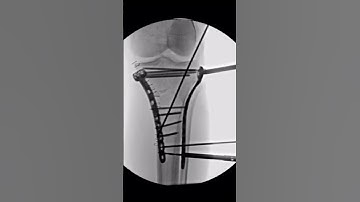

JESS Fixator Technique Basics for Proximal Tibia Fractures (Helmet Frame)